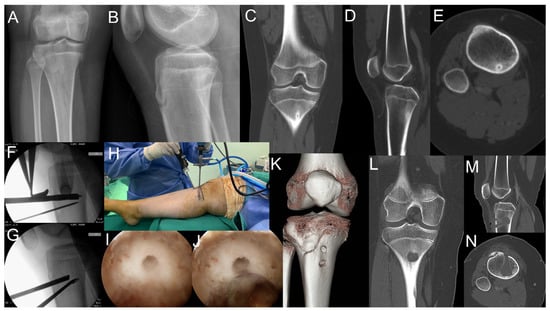

2.1. Case 1